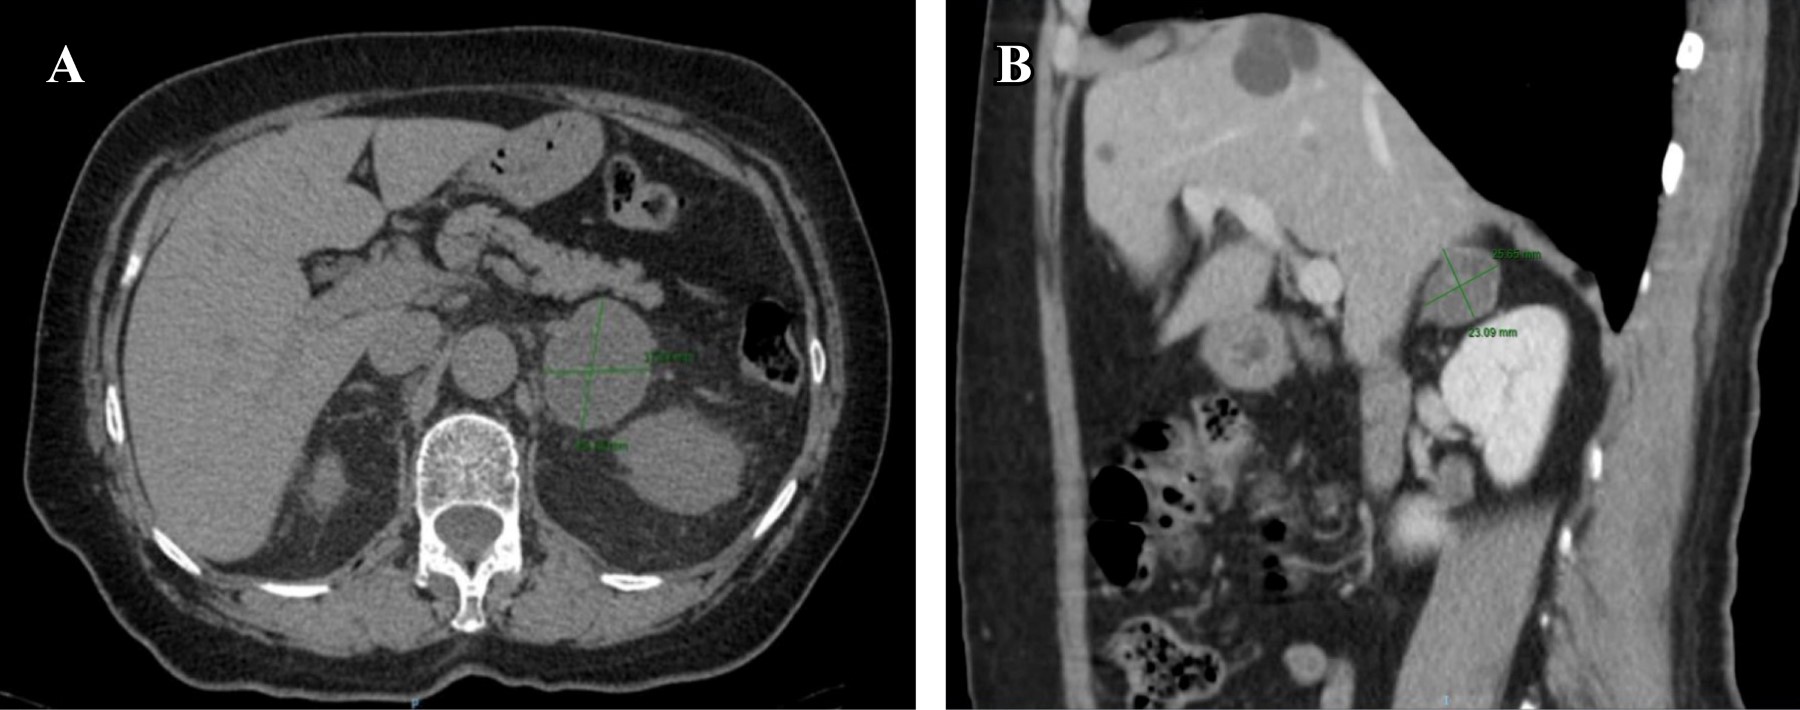

Figure 1

Figure 2

Figure 3

Figure 4

Figure 5